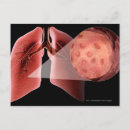

Inflammad luftväg under en astmaattack vykort

Pris21,00 kr

Illustration av en astmaattack från pollen poster

Pris343,00 kr